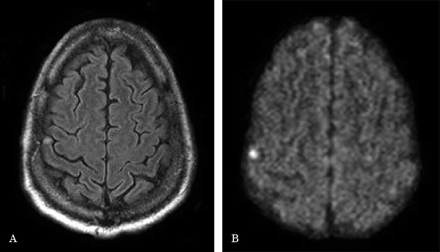

51岁的右撇子的人与高血压但没有药物呈现急性发作后的第二天在左手的指尖麻木。肢端感觉异常是局限于左第三和第四的手指远端方面。神经系统检查发现减少感觉轻触和针刺在左边第三和第四远端趾骨。两点歧视受到了损害,立体感觉和graphesthesia没有测试。剩下的考试是不正常。头部CT的表现是正常的。第二天,diffusion-weighted大脑的核磁共振显示限制高信号区正确的躯体感觉皮质。他的症状在3天内解决。颈动脉超声心电图,霍尔特监视和多角度是正常的。他于阿司匹林和美托洛尔日出院。

报告的纯感官中风的皮质病变是罕见的。1、2通常,模糊的感觉迟钝的投诉和涉及指尖和手的感觉异常是由于压腕管综合症等疾病,颈神经根病,远端周围神经病变或换气过度综合征。侧感觉赤字包括脸,胳膊,腿,主要是由于丘脑病变。当一个或两个部分的侧方,通过临床检查病变的定位更可疑。在这个病人,纯粹的感官中风是由于一个小梗死皮质区域的大脑中动脉造成的,据推测,由栓子来源。虽然没有为我们的病人的中风病因进一步评估,发现颈动脉栓子来源应该追求的,特别是在复发性感觉异常的设置(图)。